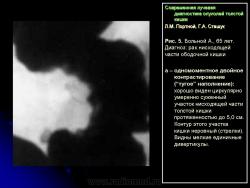

1) утолщение стенки, неровность контура и сужение просвета одного из участков кишки (рис. 5);

2) сохранение на расправленной от естественной складчатости поверхности слизистой кишки небольшого участка бариевой взвеси (типа звездочки или другой конфигурации) диаметром от 0,5 до 1,5 см – симптом ранних признаков опухоли (рис. 6);